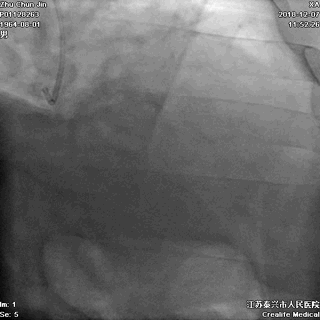

三、冠状动脉造影

▲左冠无严重狭窄

▲右冠不好找呀!